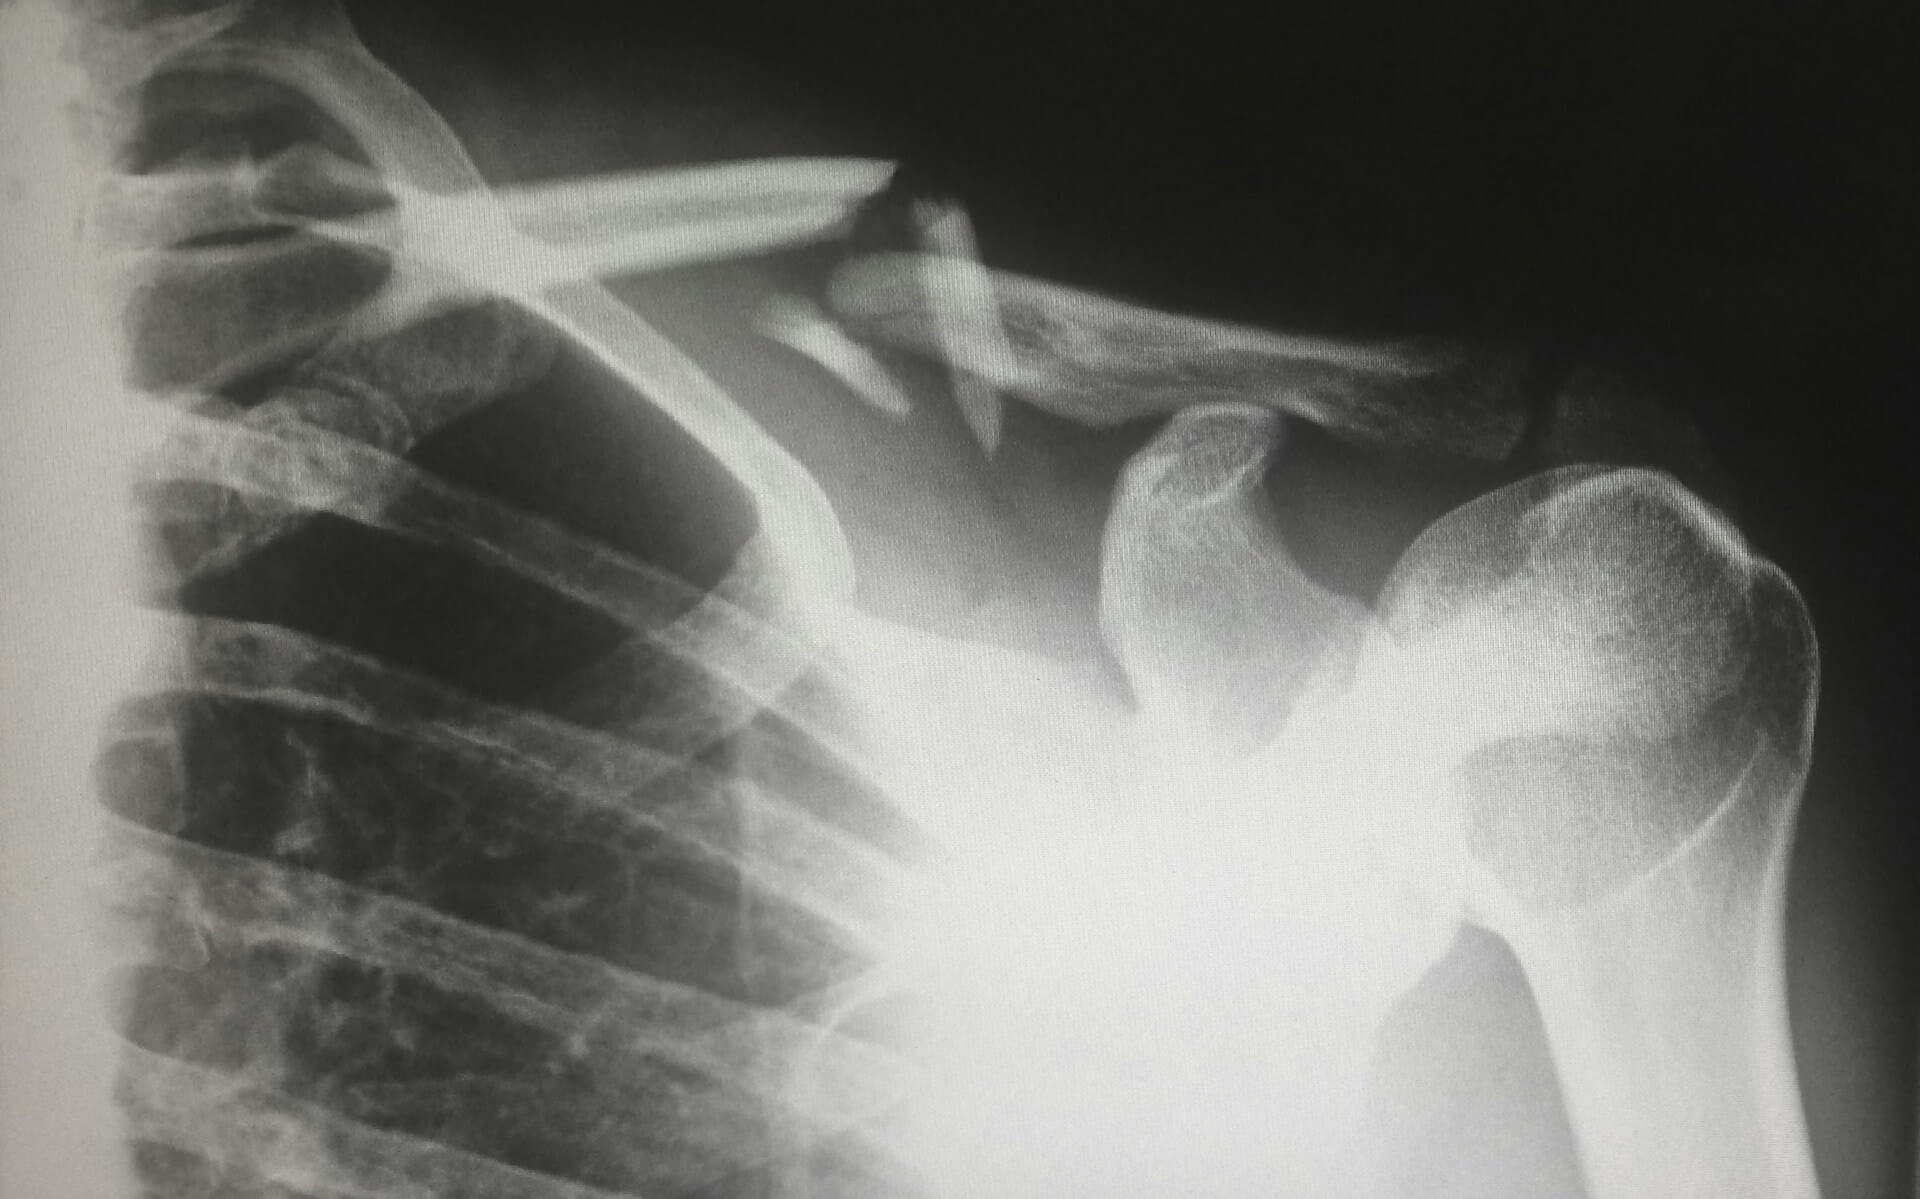

HA in Fracture Healing and Recovery

When a bone fracture occurs, healing depends on the interplay between cellular regeneration, vascularization, and extracellular matrix remodeling. Studies have demonstrated that applying HA in conjunction with bone grafts or autologous stem cells accelerates the formation of new bone tissueHA supports bone healing in three major phases:

Inflammation reduction: HA minimizes oxidative stress and swelling in the early healing stage.

Cell proliferation: It promotes the proliferation of osteoblasts and chondrocytes.

Bone bridging: HA stimulates the production of growth factors that connect broken bone fragments and enhance mineral deposition.

This regenerative role makes HA an appealing additive in surgical procedures involving bone grafting or orthopedic repair.